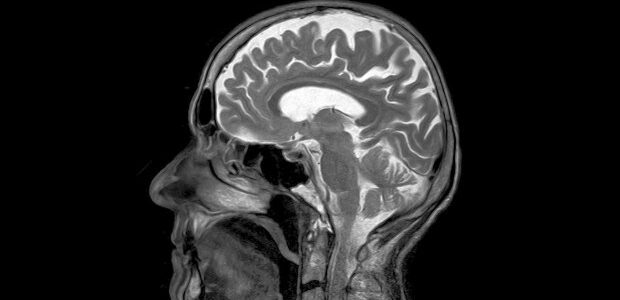

Το τεστ μετρά τα επίπεδα μιας «φωσφορυλιωμένης» μορφής της πρωτεΐνης ταυ, η οποία σχηματίζει παθολογικά συσσωματώματα στον εγκέφαλο των ασθενών με Αλτσχάιμερ.